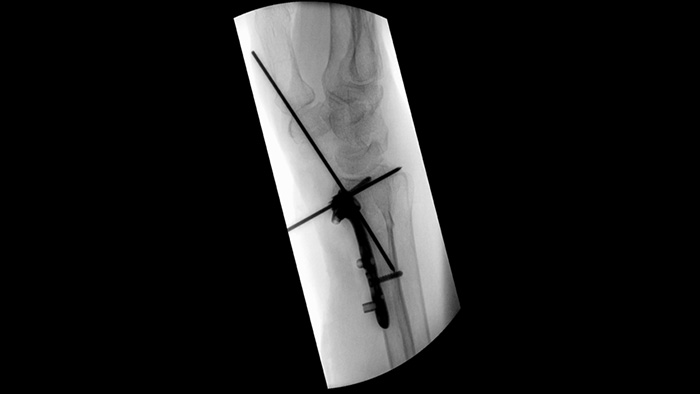

Beim Einsetzen von Pedikelschrauben für eine Spondylodese oder die Behandlung einer Fraktur sind vollste Konzentration und Teamarbeit gefragt. Laut einer Anwenderstudie ermöglichen die Navigationshilfen des Unify Workflows reibungslosere Interaktionen und weniger Abstimmungsfehler bei chirurgischen Teams.1